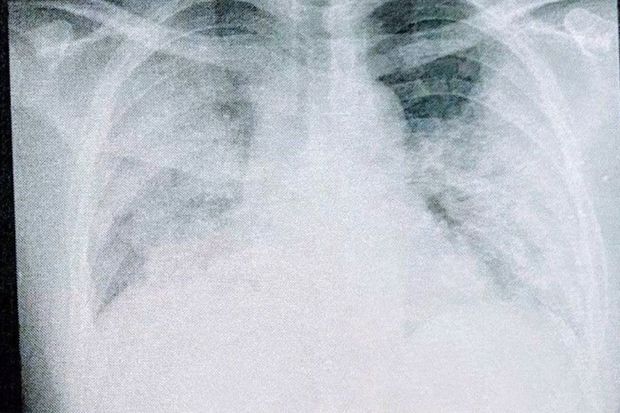

左・9月2日、愛知のセカンドオピニオン病院の入院時、右・9月6日、同病院の退院時 (写真:取材者提供/東洋経済オンライン)

[写真 6/7枚目] 左・9月2日、愛知のセカンドオピニオン病院の入院時、右・9月6日、同病院の退院時 (写真:取材者提供/東洋経済オンライン)